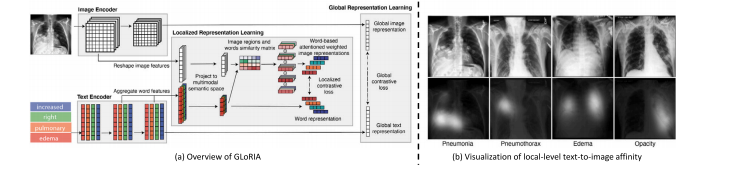

Fig. 7. Illustration of the semantic-driven contrast proposed by GLoRIA (Huang et al., 2021). (a) Overview of GLoRIA, which performs multi-scale image–text alignment based oncross-modal semantic affinity. (b) Visualization of the semantic affinity learned by GLoRIA.

图7:由GLoRIA(黄等人,2021)提出的语义驱动对比的图示。(a)GLoRIA的概述,它基于跨模态语义亲和性来执行多尺度图像-文本对齐。(b)由GLoRIA学习到的语义亲和性的可视化展示。